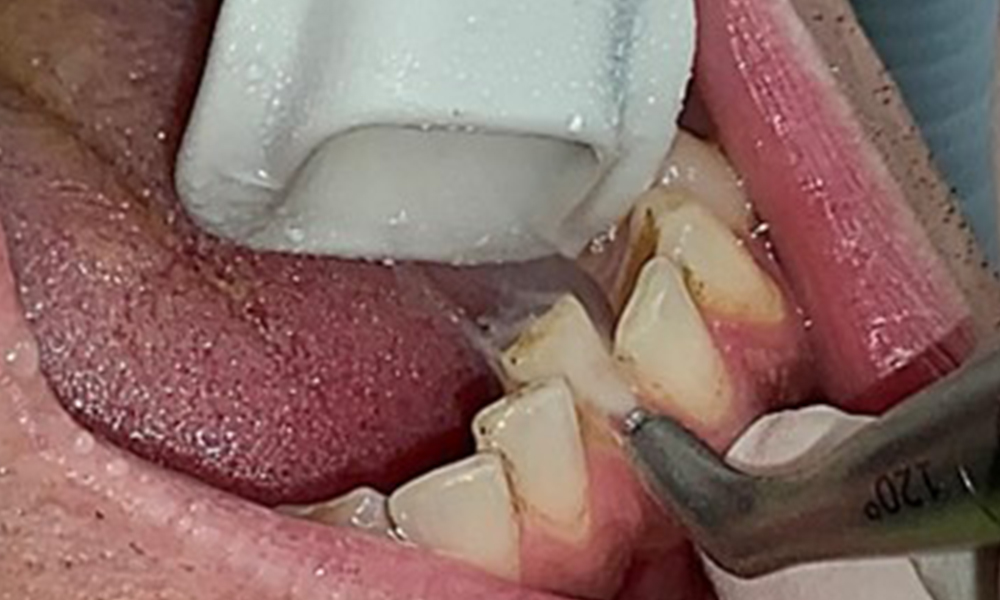

Close-up view of teeth

Fig. 5: Close-up view of teeth 45 to 47. The green arrows show dental attrition and erosions of the buccal cusps with partial enamel loss, © Dr R. Krapf

The patient has full dentition with a total of 28 teeth. There were noteworthy erosions and attritions. (Fig. 4, Fig. 5). Due to bruxism, the patient has been wearing a splint with an adjusted bite block at night for many years. The erosions were caused by long-term consumption of isotonic beverages. No periodontal bone loss or active caries were observed.